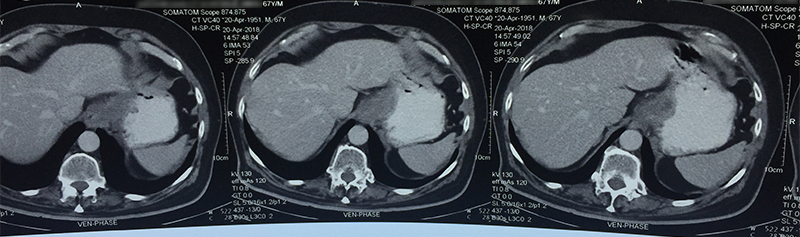

63 year old male patient was diagnosed with cancer of upper part of stomach. Patient was fit for a curative surgery on investigations. However a staging laparoscopy (endoscopy of the abdominal cavity – a type of surgery prior to main surgery) revealed a solitary deep seated lymph node spread even missed by PET-CT scan. An intraoperative frozen section histopathology (rapid test) confirmed the cancer in the lymph node. A chemoport (special system for delivering chemotherapy to avoid the trouble of searching patent veins) was inserted during the same surgery. Chemoport insertion is a surgery done regularly for patients in need of chemotherapy. Patient received 8 cycles of chemotherapy and then underwent a repeat PET-CT scan to confirm absence of metastasis. Complete stomach (including cancer bearing part) along with draining lymph nodes (lymphadenectomy) was removed successfully 4 weeks after the last cycle. A gap of 4-6 weeks is mandatory between chemotherapy cycle and major surgery to reduce risk of postoperative complications. He was put back on chemotherapy 6 weeks after the surgery and received 6 more cycles. Patient is fit and alive for 1 & ½ years since surgery.

When a stomach cancer is suspected in any patient, he/she is subjected to an endoscopy of the stomach (internal visualization). This helps in diagnosis and taking a biopsy for confirmation. A CT scan is performed after the confirmation (though often patients come with a CT scan diagnosis) to see whether the cancer can be removed surgically. A PET-CT is performed prior to any therapy to see the spread / extent / stage of the disease. If the tumor is in early stage, stomach (part / full depending on which part of stomach is involved and extent) along with the tumor and surrounding lymph nodes is removed and small intestine is joined with the proximal stomach or esophagus. If the tumor is small and lymph node spread is less, this operation is done laparoscopically. A chemoport may also be placed at this time for postoperative chemotherapy (adjuvant) unless it is a very early stage disease. Very early stage cancer can sometimes be removed through an endoscopic procedure (endoscopic mucosal resection --EMR / endoscopic submucosal dissection – ESD) under the guidance of an endoscopic ultrasound equipment. Unfortunately this is very rarely possible in Indian patients since disease is advanced by the time it is diagnosed.

If the disease is advanced in the in the abdomen and / or spread to organs like liver, then patient is given aggressive palliative chemotherapy if patient is fit as we have done in some patients. Few patients will respond in a impressive manner and are able to undergo surgery that involves removal of stomach, omentum, lymph nodes, peritoneal lining etcetera. Sometimes intraabdominal chemotherapy (HIPEC) is given too. This is again followed by systemic chemotherapy. It has shown good merit in some well selected patients. However this is still a more of palliative effort and only improves survival to an extent, and will not necessarily cure the patient. Also such treatment is very expensive, has significant surgical morbidity (complication risk) and risk to life.